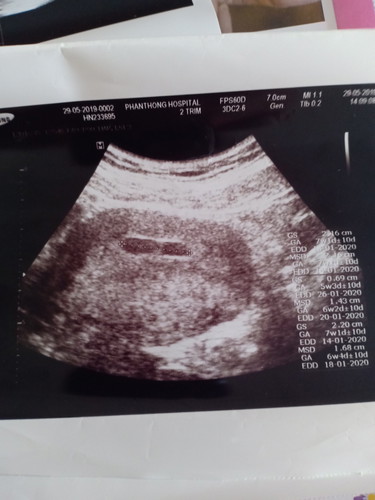

ประจำเดือนครั้งแรกมาครั้งสุดท้ายวันที่ 8 เมษา มาวันเดียวเป็นสีน้ำตาล ไปอัลตร้าซาวครั้งที่1กับครั้งที่2 โอเคค่ะ ตรงกัน วันกำหนดคลอด เหมือนกัน ประจำเดือนวันแรกครั้งสุดท้ายเหมือนกัน แต่ครั้งที่3 ทำไมประจำเดือนครั้งสุดท้าย ถึงเป็นวันที่15เมษา กำหนดคลอด20มกราคม แต่2ครั้งแรกกำหนดคลอด 13มกราคม ควรเชื่ออันไหนดีค่ะ